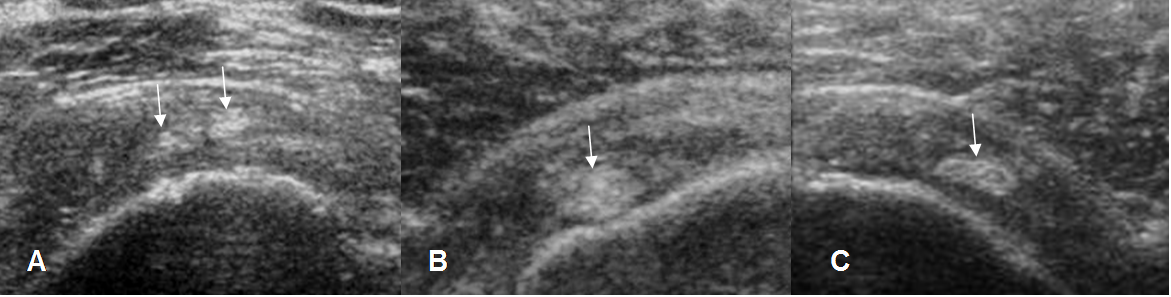

Fig 102. Ruptura parcial del supraespinoso.

A y B: Ecografía coronal. Zonas hipoecoicas en la superficie humeral, por ruptura parcial.